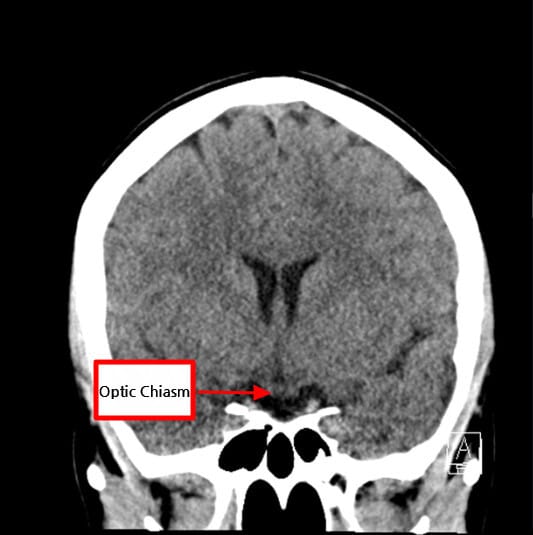

| 🟨 시야장애 (양측 반맹) |

| 시신경 교차부(Optic Chaism)를 압박하여 외측 시야가 손상됩니다. |

| ✅ 시신경 교차 압박 가능성 |

| 상방으로 확장된 종양이 시신경을 눌러 시야장애를 유발합니다. |